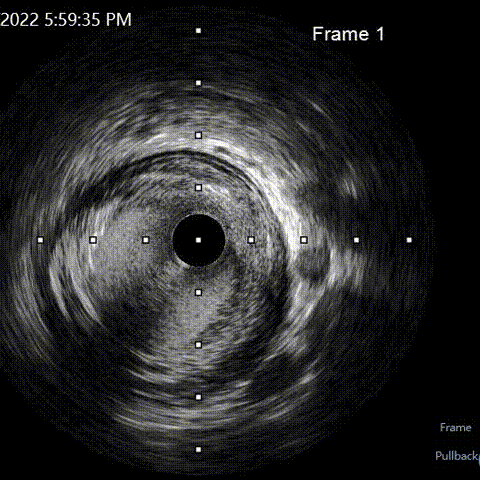

LAD pre-IVUS check RUN 1 looking for entry point

LAD pre-IVUS check RUN 2

LAD post-IVUS check RUN 3